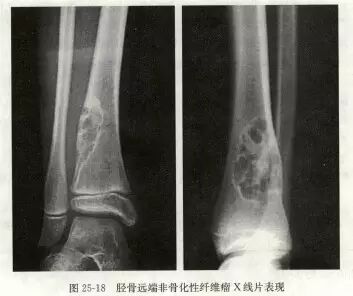

X线特征相当典型,容易作出诊断。病变位于长骨干骺端骨干的内侧,距骺板3~4cm处,未累及后者。病灶1~5cm大小不等,有的可达10cm。病变为圆形或椭圆形、偏心性生长,与骨长轴一致,但有向整个骨侵及倾向。病损内部常呈分叶状,骨皮质变薄,而髓侧边缘硬化,界限清晰。位于皮质骨附近者,从一侧突出骨外,表面骨质轻度扩张,骨质变薄。位于股骨等粗大骨内者可偏心性生长,位于腓骨等细小骨者可充满髓腔,表面骨质轻微变薄。肿瘤基底与髓腔边界处骨质轻微硬化,常呈肥皂泡沫状,可合并病理骨折。